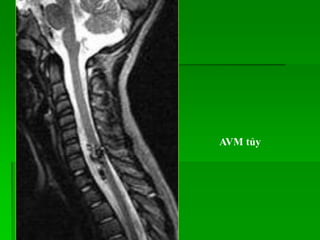

AVM tủy

BN K phổicó bất thường tín hiệu tủy xương thân sống T12, L1,2, tín hiệu thấp trên T1W, cao trên TIRM, không thấy giảm tín hiệu đáng kể trên hình out-of-phase so với hình in-phase  gợi ý tổn thương ác tính.